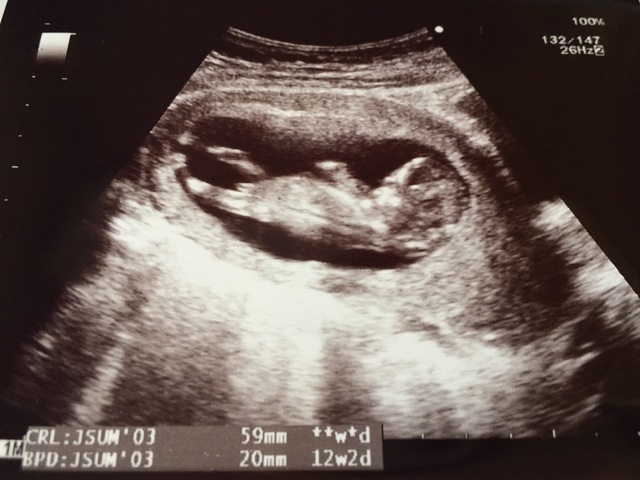

12週2日(12w2d・男の子)|リおん さん(28歳)

エコー写真撮影時のエピソード:

初産です。早期で男の子のシンボルがはっきりわかり、主人とともに喜びました。性別はどちらでもよかったですが、主人が長男ということもあり後継を考えると最低でも男の子は1人でもほしいと思っていました。

主人も私も乗り物が好きという共通点もあり、車やバイク、飛行機など男の子らしい遊びをさせてあげたいという思いもあってうれしかったです。

定期健診でのエコーでは毎回というほどチンチンが写り、日々成長していく中で睾丸もわかり男の子だね~と、どの医者にも言われました。初産のため楽しみ、不安と様々な感情がありますが、無事元気に産まれてくることを願うばかりです。